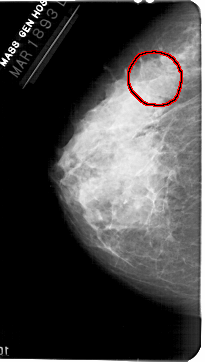

FILE: A_1361_1.LEFT_MLO.OVERLAY

TOTAL_ABNORMALITIES 1

ABNORMALITY 1

LESION_TYPE MASS SHAPE IRREGULAR MARGINS OBSCURED

ASSESSMENT 3

SUBTLETY 1

PATHOLOGY BENIGN

TOTAL_OUTLINES 1

BOUNDARY